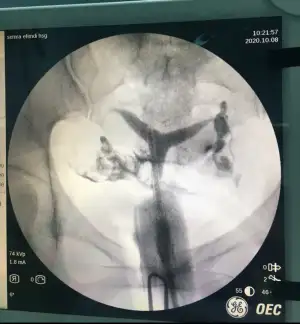

Hsg sonrasi T rahim oldugumu ogrendim. Ayrıca rahimin ileri derecede geriymis. 10 aydir cocuk sahibi olamadik dogal yollarla. Ayrica esimin morfolojisi 1di. Sayisi hareketliligi falan cok dusuktu.